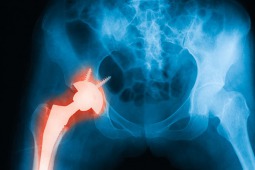

Współpraca pomiędzy American College of Reumatology i Amerykańskiego Stowarzyszenia Chirurgów Stawu Biodrowego i Kolanowego doprowadziła do opracowania wytycznych w leczeniu chorych ze schorzeniami reumatologicznymi, u których przeprowadza się wszczepienie endoprotezy stawu biodrowego lub kolanowego.

Panel amerykańskich reumatologów oraz ortopedów specjalizujących się w endoprotezoplastyce stawu kolanowego i biodrowego opracował wytyczne postępowania z pacjentami reumatologicznymi, u których planowana jest endoprotezoplastyka stawu biodrowego lub kolanowego.